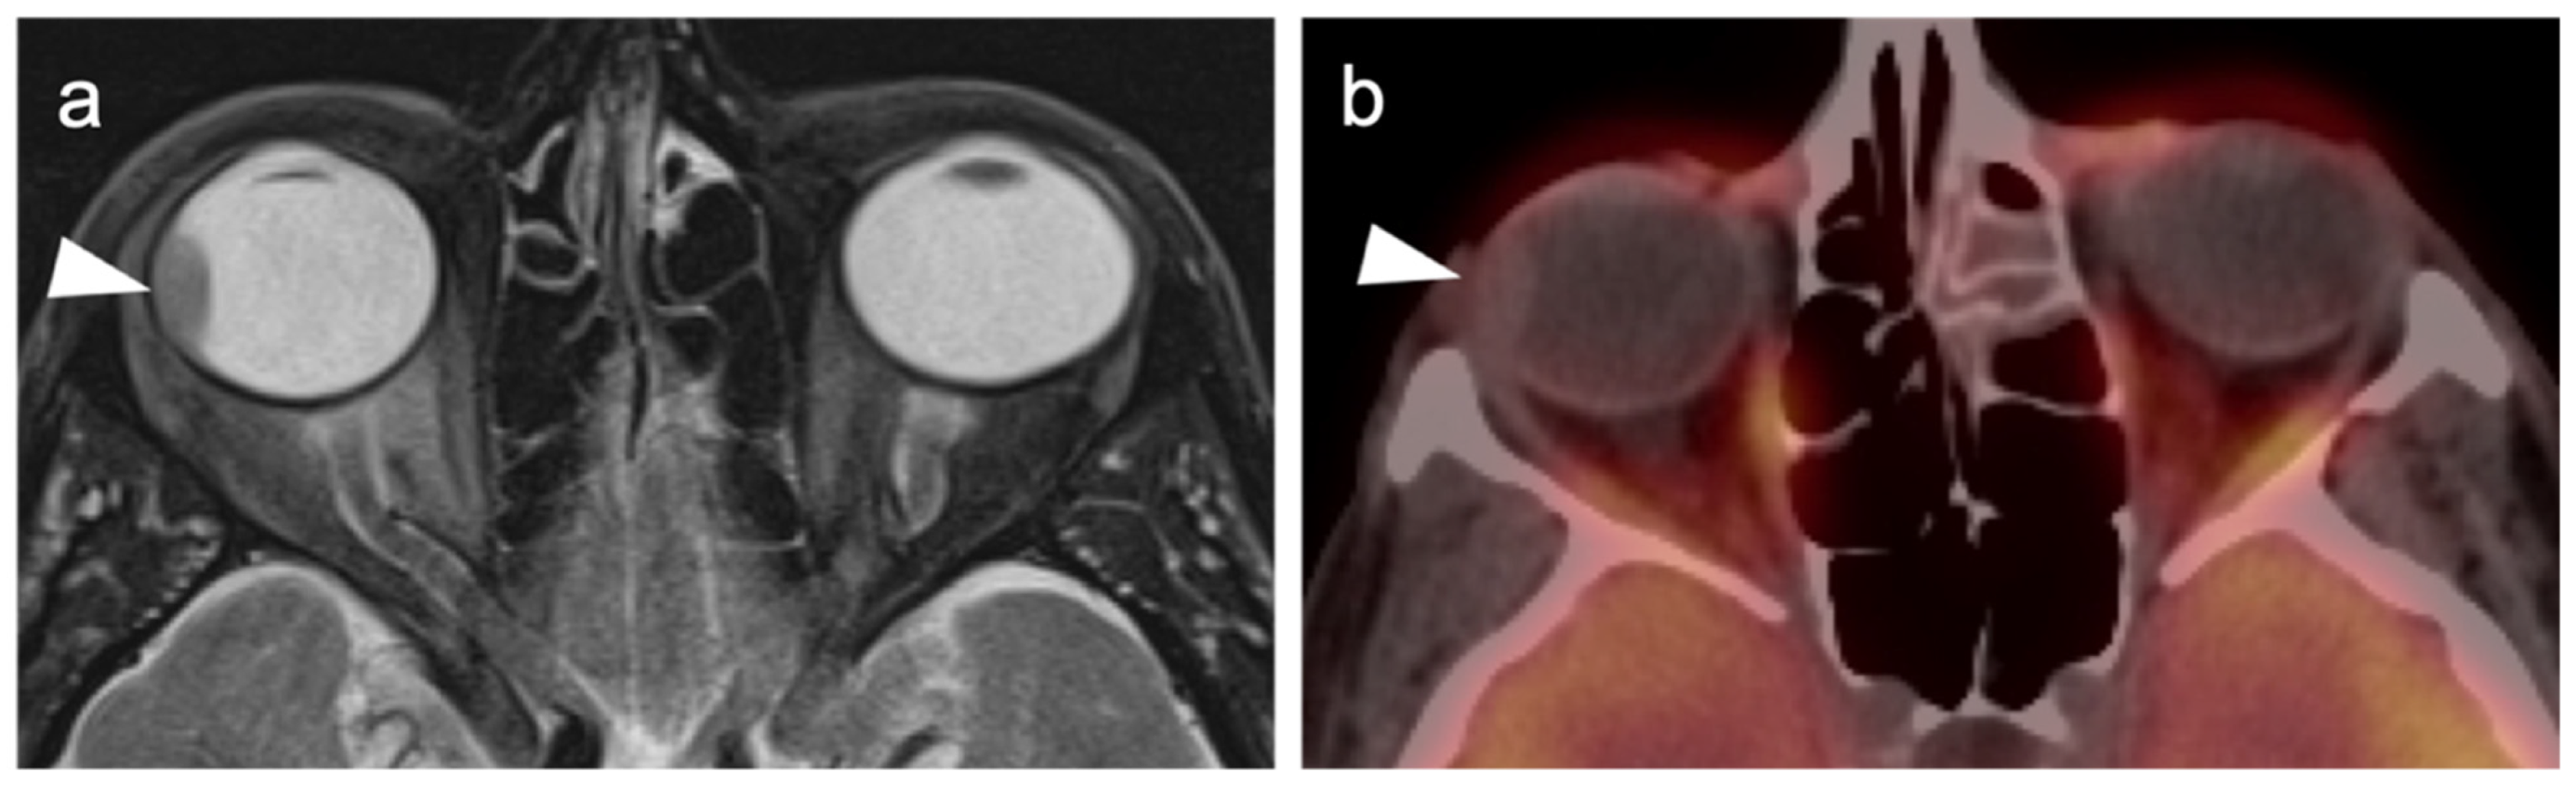

2.3.2. Ocular Melanoma